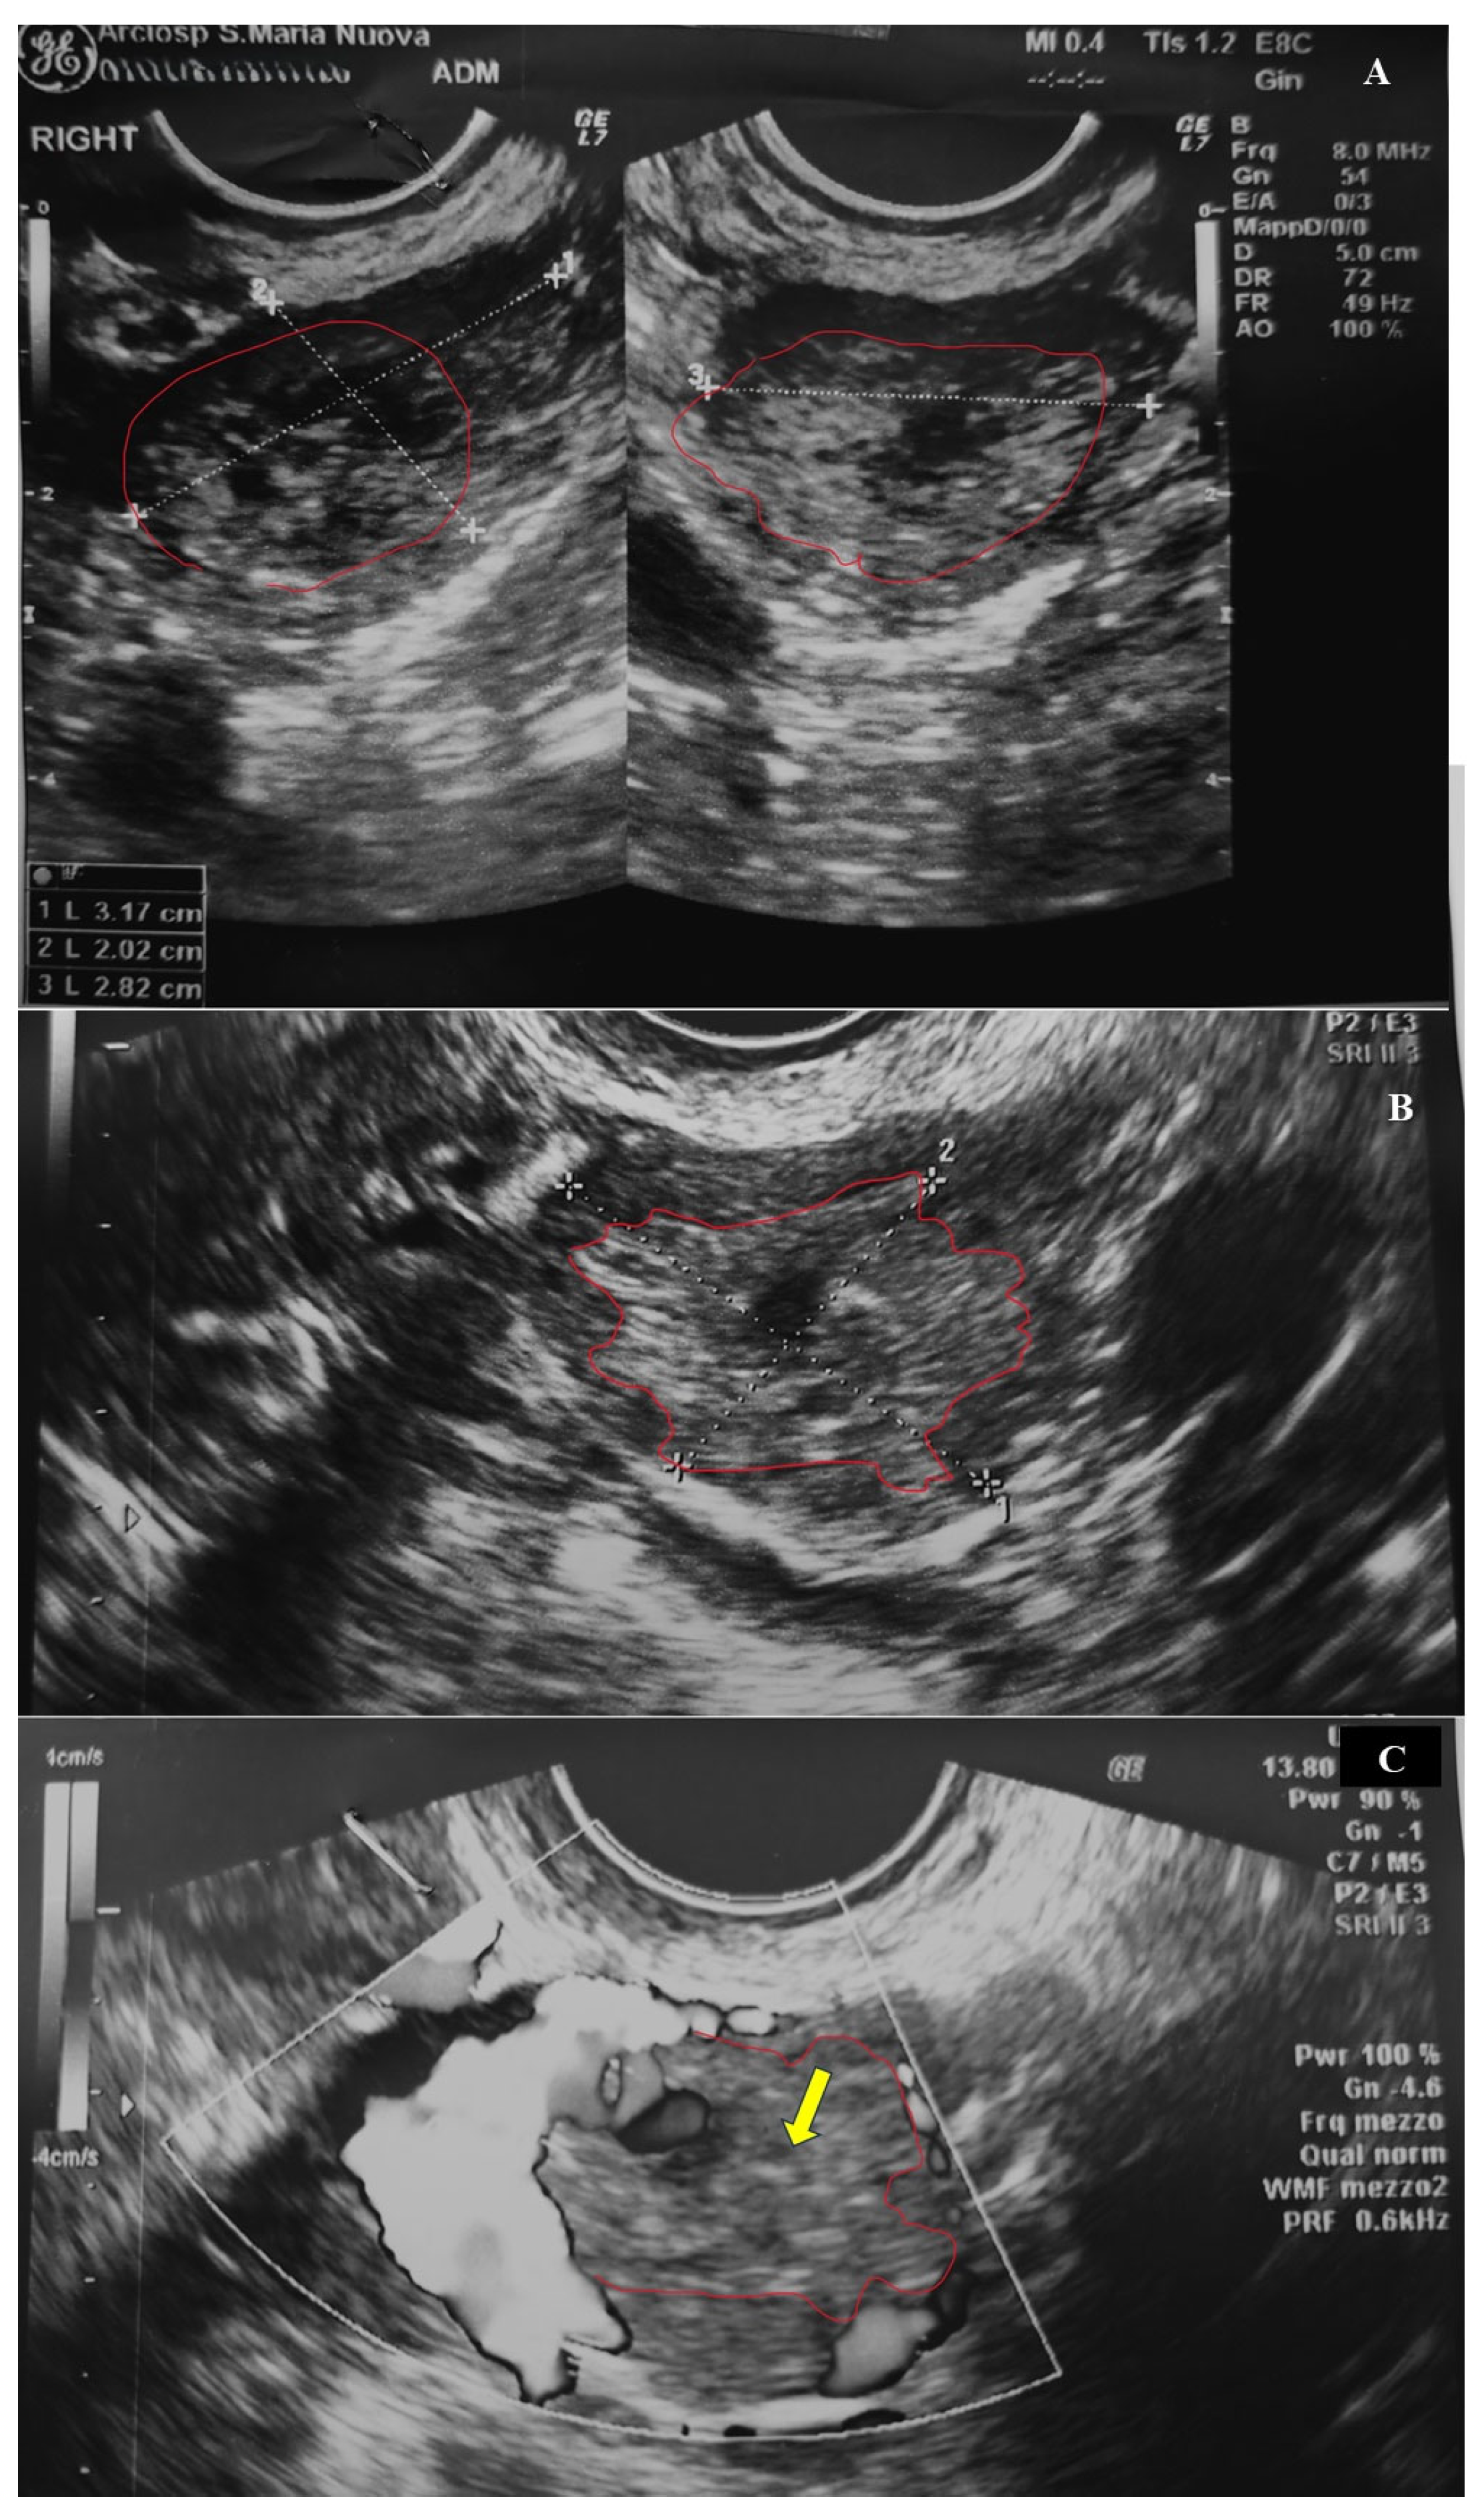

2. Case Presentation

2.1. Clinical History